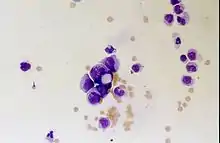

Lymphomes primitifs du SNC

Le lymphome primitif du système nerveux central représente environ 2 pour cent à 3 pour cent de toutes les tumeurs cérébrales chez les patients ayant un système immunitaire normal. Ils surviennent plus fréquemment chez les hommes de plus de 55 ans jusqu'à 60 ans. Près de la moitié de tous les lymphomes surviennent chez des patients de plus de 60 ans et environ un quart chez des patients de plus de 70 ans. L'incidence semble augmenter avec l'âge, mais la raison n'est pas encore claire. Les patients dont le système immunitaire est affaibli sont plus à risque de développer un lymphome du SNC, de sorte que ceux qui ont subi une greffe d'organe ont une immunodéficience congénitale ou une maladie auto-immune, ou sont infectés par le virus de l'immunodéficience humaine. Les lymphomes cérébraux associés au VIH sont associés au virus d'Epstein-Barr, en particulier chez les patients dont le nombre de lymphocytes CD4 est inférieur à 500 cellules par millimètre cube dans le sang. La plupart des lymphomes du SNC sont des lymphomes diffus à grandes cellules B.

Les patients souffrent d'une variété de symptômes caractéristiques d'une lésion massive focale ou multifocale. L'IRM montre généralement des tumeurs avec un rehaussement de contraste homogène au sein de la substance blanche périventriculaire profonde. La multifocalité et le rehaussement inhomogène sont typiques des patients dont le système immunitaire est affaibli. L'analyse du lymphome du SNC est extrêmement importante dans le diagnostic différentiel de la néoplasie cérébrale. Il est à noter que l'administration de corticoïdes peut entraîner la disparition complète du rehaussement, rendant difficile le diagnostic des lésions. Par conséquent, si un lymphome du SNC doit être pris en compte dans le diagnostic différentiel, les corticoïdes doivent être évités à moins que l'effet de masse ne provoque un problème grave et immédiat chez le patient.

La biopsie de la lésion suspectée est cruciale. Contrairement au lymphome systémique à grandes cellules B, dans lequel la chimiothérapie et la radiothérapie sont efficaces et le traitement des lésions localisées est curatif, le lymphome du système nerveux central répond généralement au traitement initial mais réapparaît ensuite. Comme pour le lymphome systémique, le rôle de la chirurgie est principalement limité à l'obtention d'échantillons de tissus appropriés pour le diagnostic.

Dans le passé, la radiothérapie était administrée à l'ensemble du cerveau (panencéphalique). La médiane de survie est d'environ 12 même avec des lésions localisées Mois. La récidive affecte généralement le site de la blessure précédente ainsi que d'autres régions. Les réponses à la chimiothérapie sont plus prometteuses. Les essais cliniques dans lesquels le méthotrexate à haute dose seul a été utilisé comme premier traitement et la radiothérapie a été retardée jusqu'au moment de la rechute ou de la progression ont montré une meilleure survie globale que la radiothérapie seule. Encore plus efficace était la combinaison de méthotrexate, vincristine, procarbazine, méthotrexate intrathécal, cytarabine et radiothérapie panencéphalique et cytarabine, ou l'utilisation d'une chimiothérapie intra-artérielle avec méthotrexate intra-artériel, cyclophosphamide injecté par voie intraveineuse et étoposide après modification du sang. barrière cérébrale avec du mannitol. La médiane de survie sous méthotrexate était de 24 jusqu'à 40 mois beaucoup plus élevé qu'avec la radiothérapie seule (extrêmes 24 jusqu'à 40 mois). Dans certains cas, la radiothérapie n'est utilisée que pour les rechutes lorsqu'il y a une régression initiale avec la chimiothérapie. Des cas de survie longue ont également été rapportés sans radiothérapie.

La radiothérapie panencéphalique est associée à un risque élevé de développer une démence ou une leucoencéphalopathie . Ce risque pourrait être réduit en développant des stratégies efficaces de contrôle des tumeurs qui évitent la radiothérapie panencéphalique. Le traitement initial des patients dont le système immunitaire est affaibli consiste à réduire les causes de l'immunosuppression. Le pronostic de ces patients est généralement pire que celui des patients dont le système immunitaire est normal. En raison des infections tumorales qui l'accompagnent et d'une condition physique généralement sous-optimale, la chimiothérapie ne peut souvent pas être effectuée chez ces patients immunodéprimés. Comme pour les autres tumeurs cérébrales, la réponse aux traitements dépend de l'âge et de la condition physique.